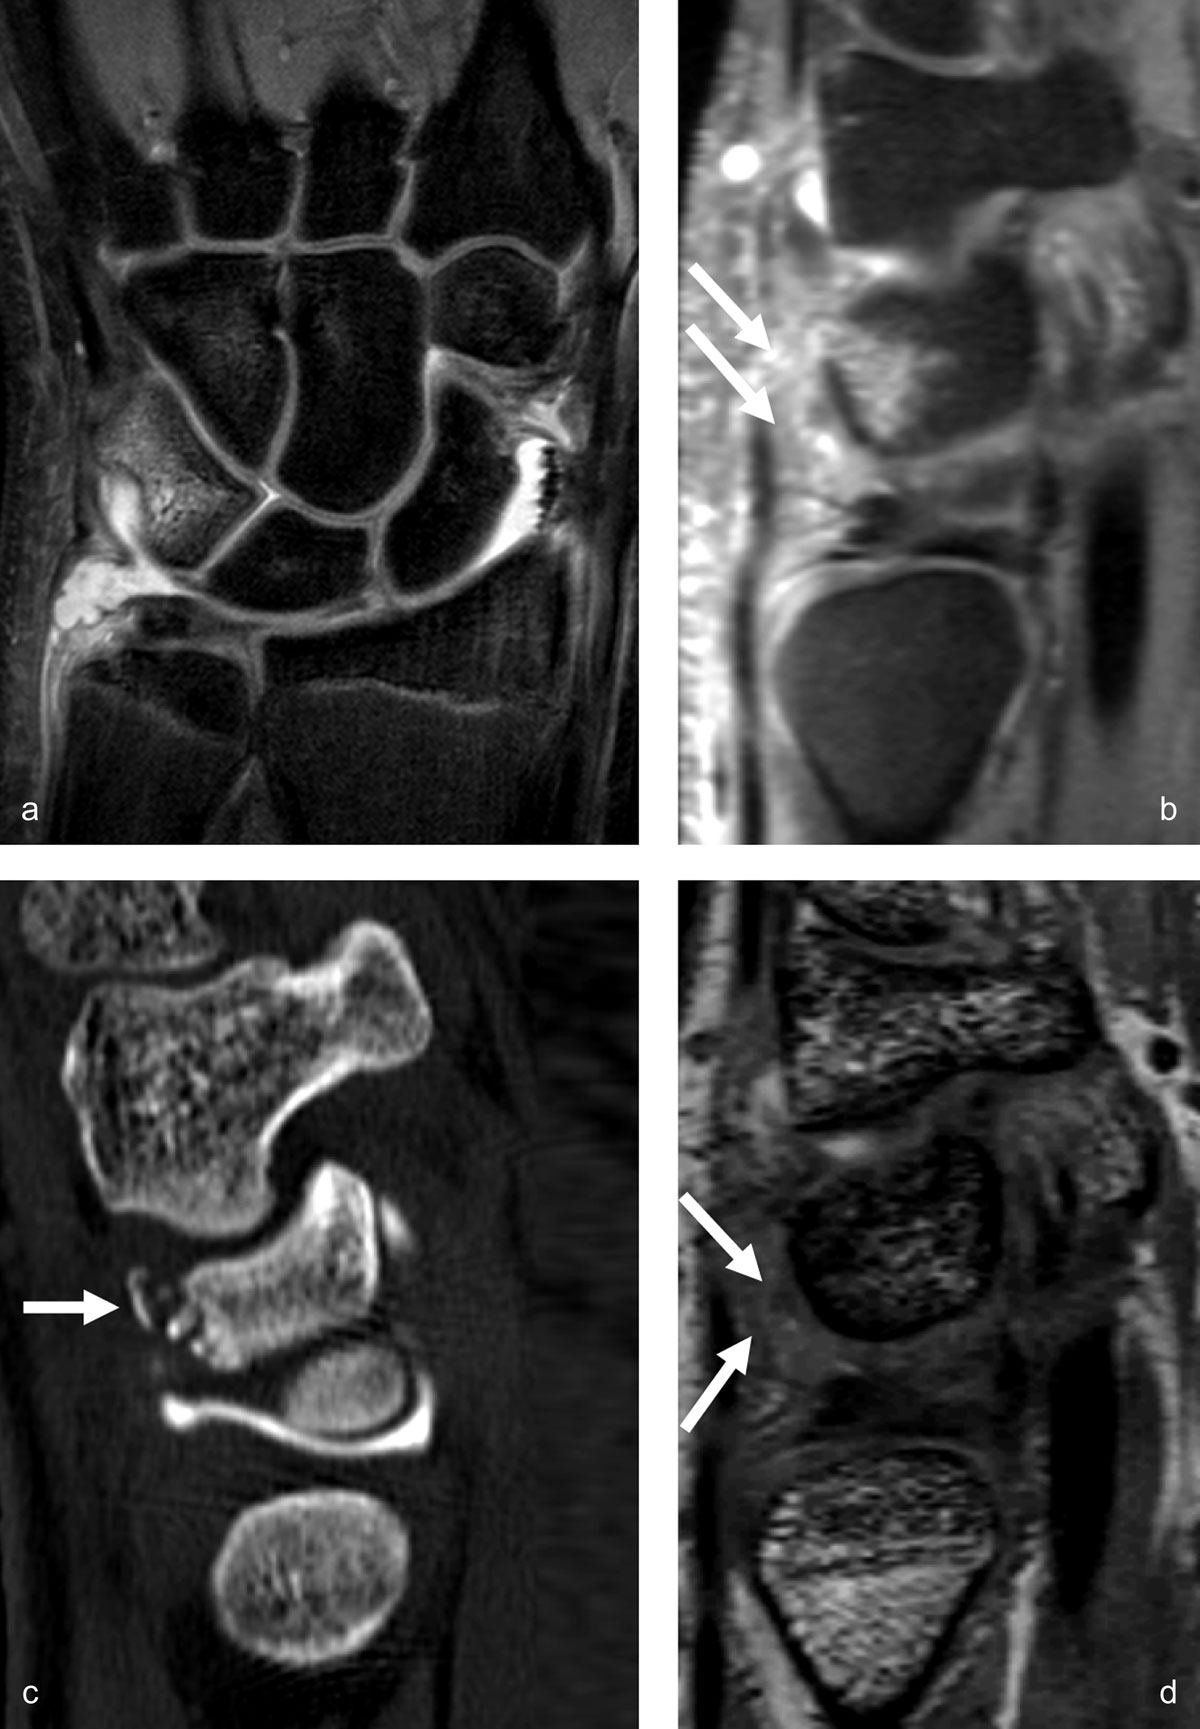

Figure 5

Triquetrum occult fracture with synovitis in the prestyloid recess and traumatic bone avulsion with subacute edematous infiltration of the dorsal capsular ligaments. MR arthrography performed 12 days after a fall on an outstrechted hand allows detection of bone marrow edema in the dorsal part of the triquetrum on coronal proton-density fat-saturated images (a) and sagittal 0.4mm reconstruction from a 3D proton-density fat-saturated sequence (b), as well as edematous infiltration of the surrounding dorsal soft tissues (arrows on b). The dorsally avulsed bony fragments are better seen on CT (arrow on c). The dorsal capsular infiltration (mostly the extrinsic dorsal radiotriquetral ligament) with low to intermediate signal intensity is also depicted on the sagittal reconstruction from the 3D DESS sequence (arrows on d).